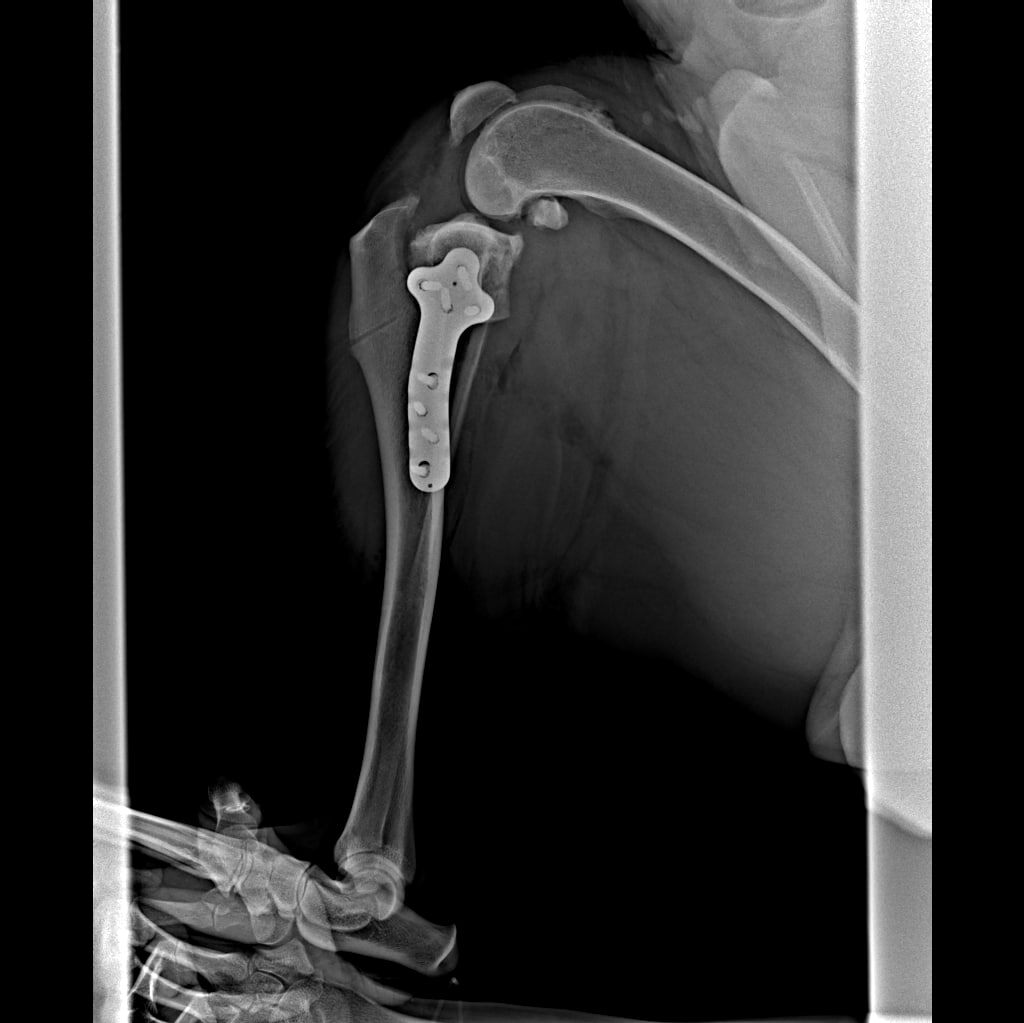

Эксперт Михаил Александрович Дудочкин недавно завершил лечение пациента с разрывом передней крестообразной связки. Это довольно частая травма у собак, которая может привести к боли, ограничению движений и даже хромоте. Для лечения мы использовали метод ТПЛО – стабилизацию коленного сустава с помощью транспозиции тибиальной пластинки.

ТПЛО – это операция, направленная на коррекцию угла в коленном суставе после разрыва передней крестообразной связки. Метод позволяет стабилизировать колено и восстановить его функциональность, обеспечив питомцу движение без боли. Такой подход помогает избежать дальнейших осложнений и остаться активным и здоровым.

✅ После операции ТПЛО колено было стабилизировано, и за два месяца коленный сустав полностью восстановился. Наш пациент вернулся к активной жизни, и мы очень рады результатам.